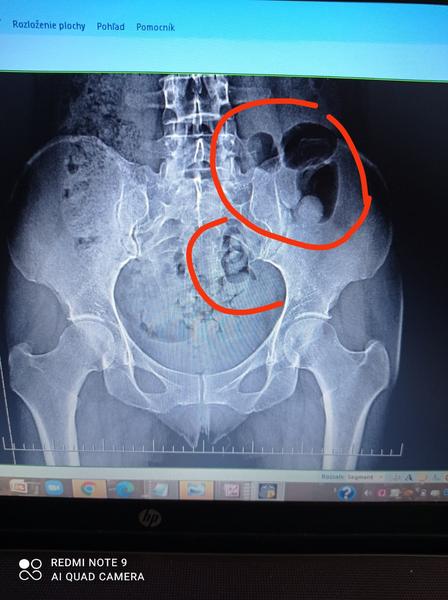

Dobrý deň .Rozumie sa niekto prosím RTG snímkam? Vedel by niekto popísať výsledky kým pôjdem k dr aby som bola trochu"v obraze ".Ďakujem pekne 🙏

Nie som lekár, trochu snímky poznám. Veľké zmeny tam nevidím. Čo sa týka chrbtice celkom fajn. Trochu zmeny v dolnej driekovej oblasti, ale nič výrazné. Bedrové kĺby sú tiež celkom dobré, akurát pravý trochanter má menšie zmeny. Možno ti to môže spôsobovať bolesti akoby pravého boku. Trochanterickú bursitídu.

Možno to nie je presné.

@joesvk bolesti mám v ľavej časti kĺbu ,si kĺbu a zadku ..a tieto čierne fľaky sú ok ?

@timejicka Tie fľaky sú hrubé črevo. Sú OK 🙂Bolesti samozrejme môžeš mať kdekoľvek, môže tam byť napr. zápal. Ale nejaké výrazne degeneratívne zmeny, ktoré by bolo už vidieť na Rtg snímku nie sú. Teda ja nevidím, možno nevidím dobre.